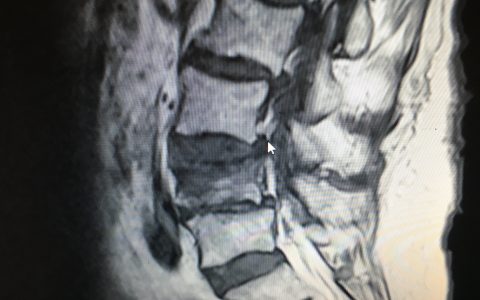

Περίπτωση Πα. Γι.: Επανεγχείρηση σκολίωσης ενηλίκων

Η κα Πα.Γι. 61 ετών, έπασχε από σκολίωση της σπονδυλικής στήλης από νεαρή ηλικία. Σε ηλικία περίπου 40 ετών άρχισε να παραπονιέται για πόνο στην οσφυϊκή μοίρα της σπονδυλικής στήλης. Η αντιμετώπιση του πόνου ήταν συντηρητική. Προοδευτικά ο πόνος επιδεινώθηκε παρά την αγωγή, γι’ αυτό αναζήτησε περαιτέρω θεραπευτική αντιμετώπιση. Εικ 1: Προεχειρητικές ακτινογραφίες της σπονδυλικής